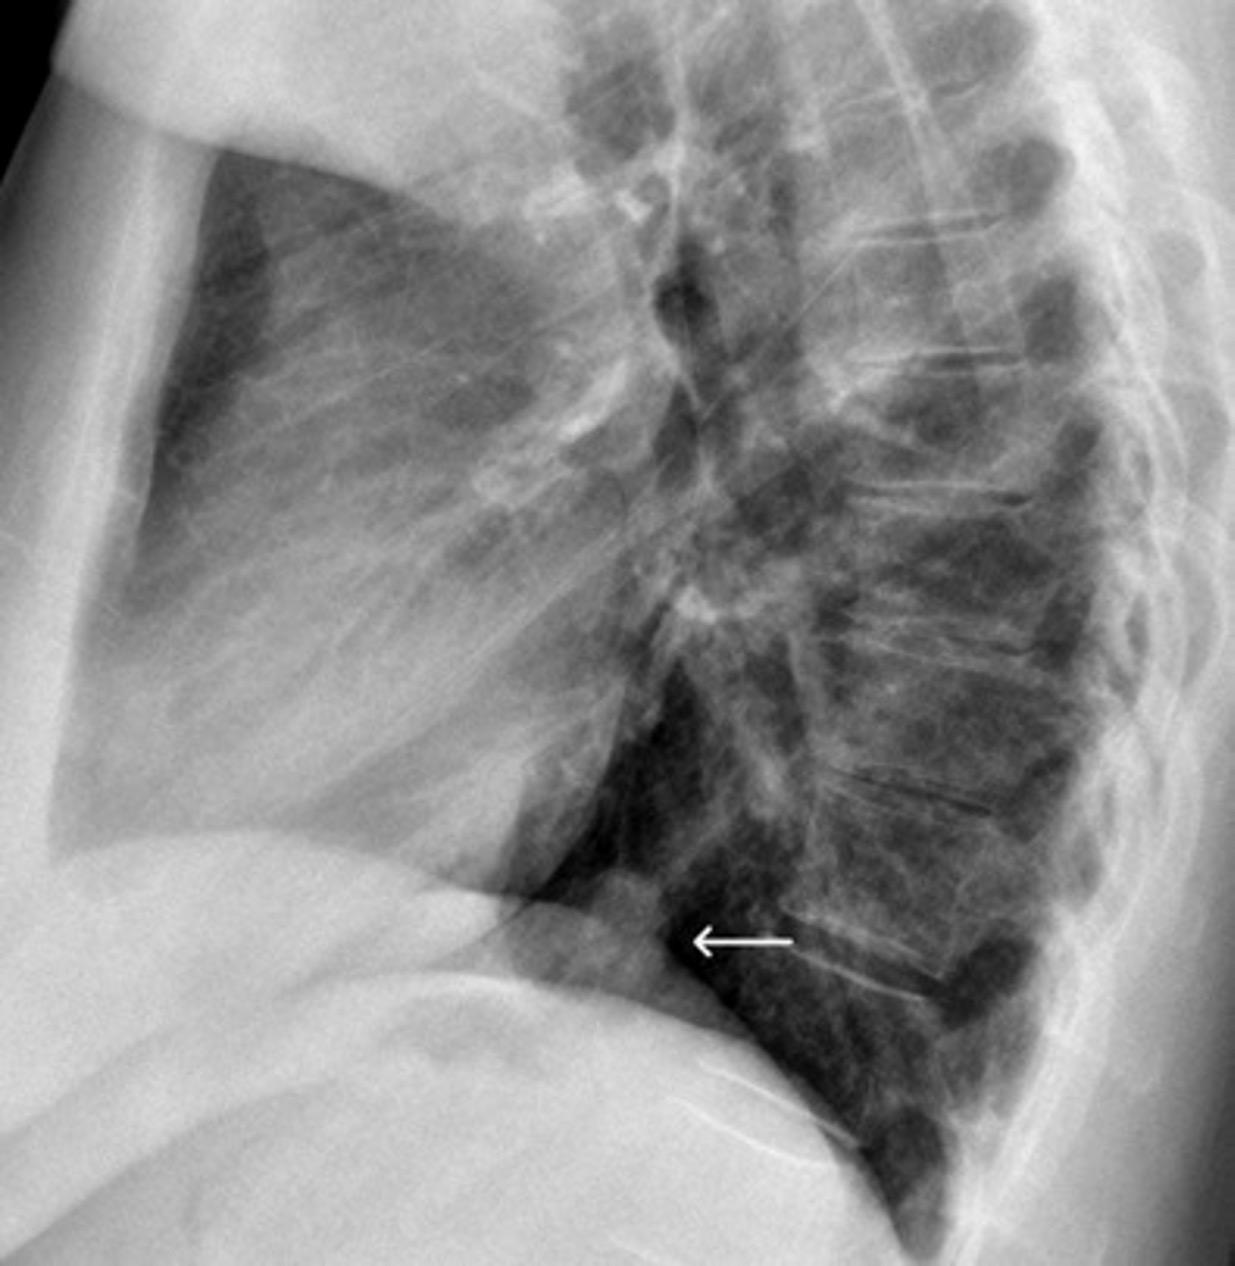

Anorexia nerviosa, Tuberculosis masiva izquierda con neumotórax y cavidades. Diseminación broncógena derecha con cavitación. M. complex

ZylakCM et al. Pneumomediastinum Revisited.Radiographics 2000